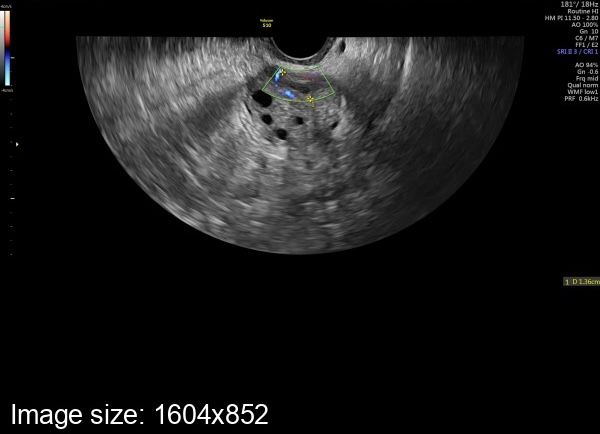

Пришла к врачу узисту , она говорит что овуляция была , но у меня раньше таких маленьких жт не было , кто разбирается подскажите

Визуально - Очень слабый кровоток в жт. Обычно вокруг жт яркое пламя. А размер жт не имеет принципиального значения.

Далее. Очень тонкий эндометрий .

Скорее всего, не было полноценной овуляции. Чтобы ответить точно сдаётся за неделю до месячных прогестерон и эстрадиол.